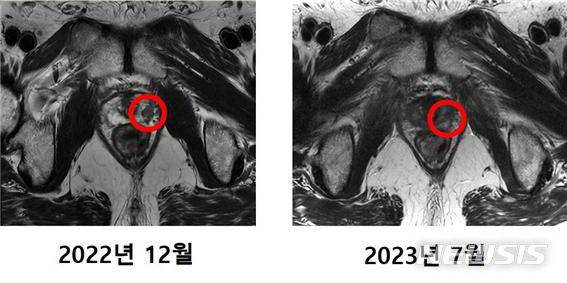

![[서울=뉴시스]국내 첫 중입자치료 환자 MRI 비교 사진. (사진= 세브란스병원 제공) 2023.09.19. photo@newsis.com.](https://img1.daumcdn.net/thumb/R658x0.q70/?fname=https://t1.daumcdn.net/news/202310/18/newsis/20231018070029599dluy.jpg)

연세암병원은 지난 4월부터 중입자 치료기 가동을 시작한 바 있다. 중입자 치료를 받은 암 환자의 암 조직이 한 달만에 제거됐으며 주변 장기 손상 등 후유증도 없었던 것으로 알려졌다.